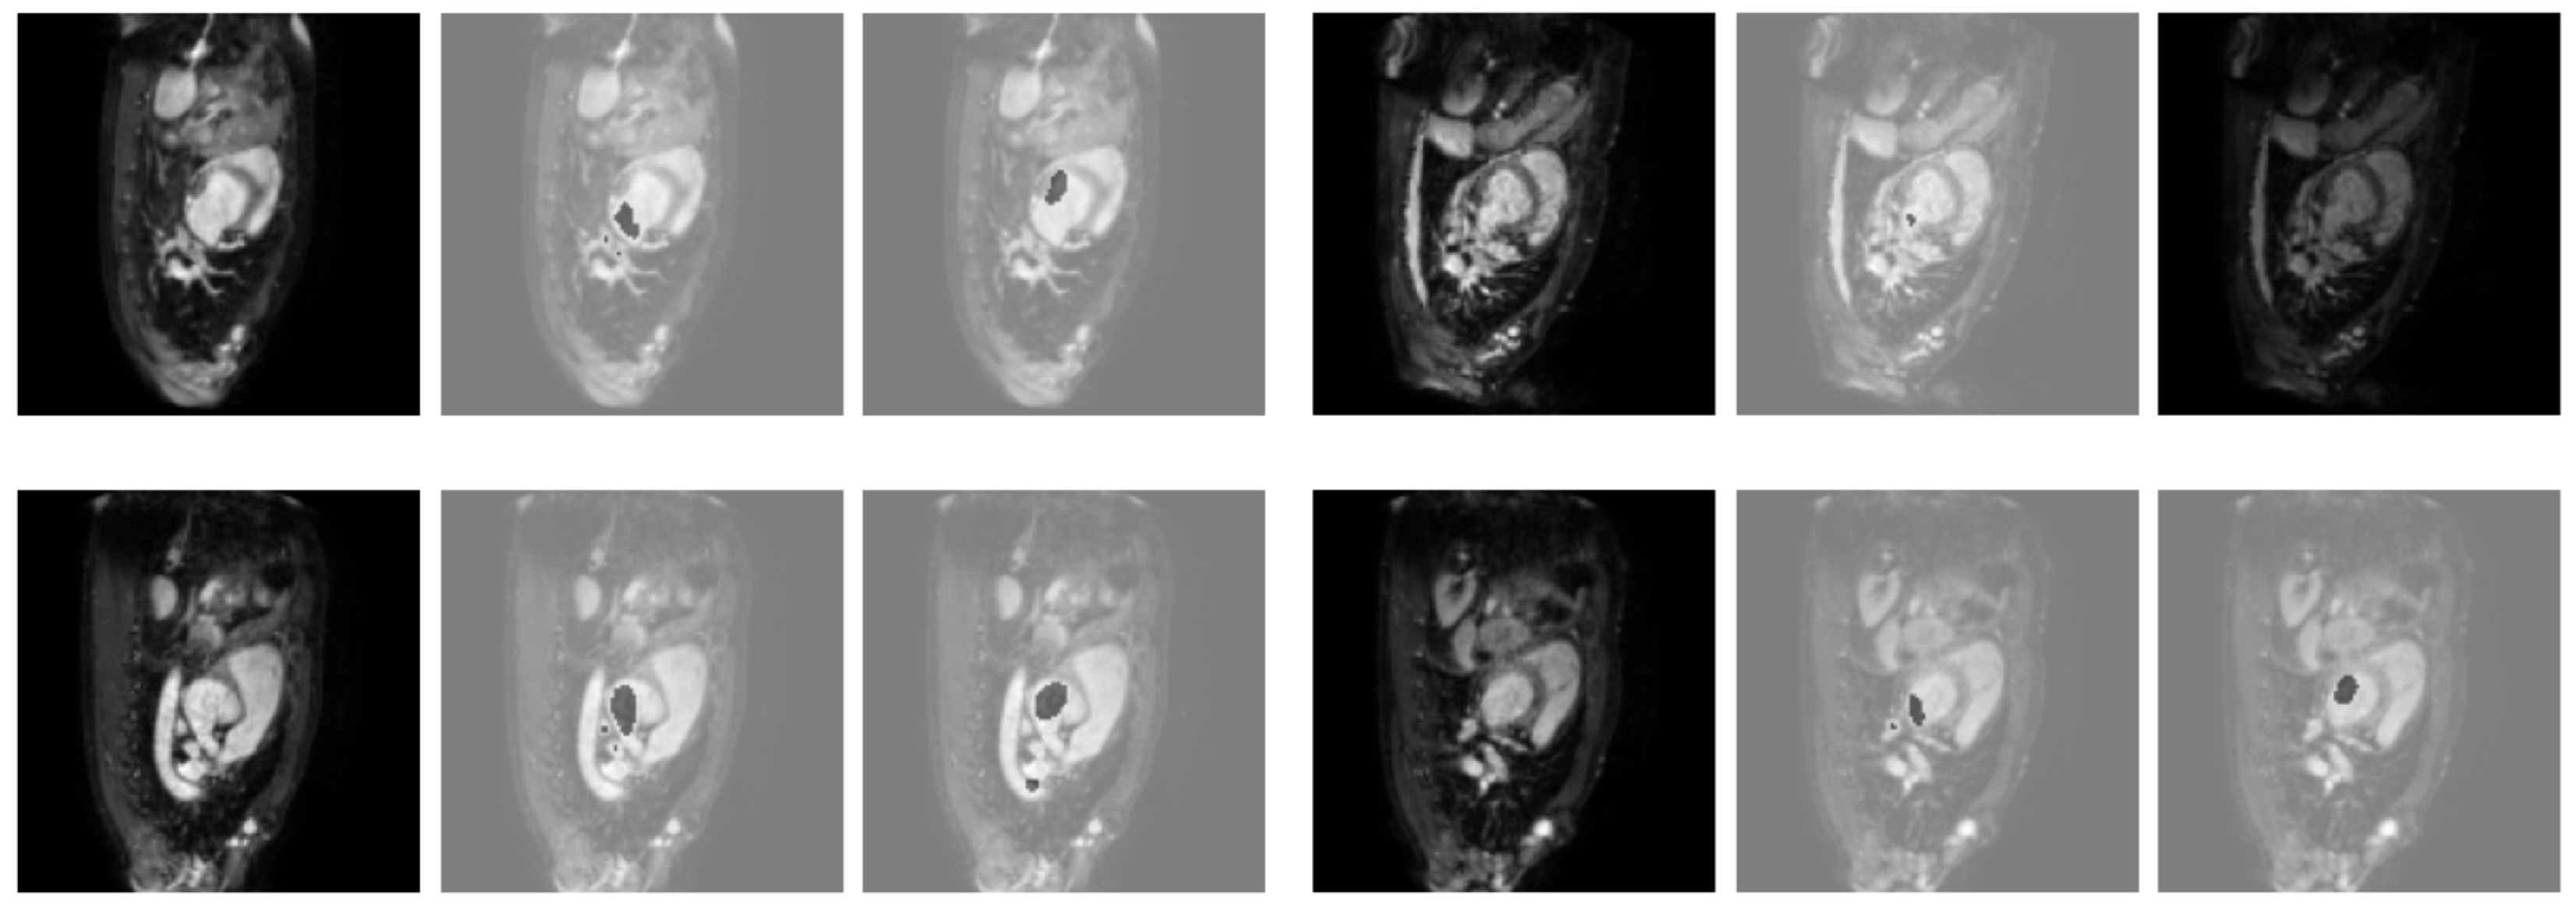

Table 4 demonstrates the successful application of SAB-Net to ventricular segmentation and the superior performance compared with that of existing approaches based on the validation results obtained on the Heart MRI dataset. SAB-Net’s average Dice value exceeded that of U-Net, the baseline, by 35.32%. We argue that the degradation problem caused U-Net to have very low Dice scores on the Heart MRI dataset. When increasing the network capacity with depth, the network performance became unsurprisingly saturated and was then quickly degraded [2]. This was also verified by our experiments, as shown in Table 4. Figure 3 illustrates an example of qualitative results obtained by U-Net, Att-UNet, and SAB-Net for the Heart MRI images.

Figure 3.

Qualitative results obtained for the heart MRI images. From left to right: ground truth, U-Net, Att-UNet, and SAB-Net.